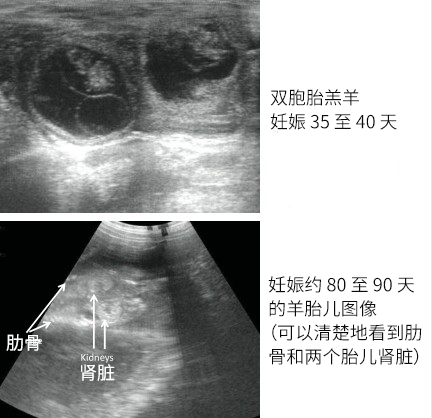

直肠超声用于母羊妊娠检测,是指通过将线阵探头 (通常是 5–7.5 MHz) 插入羊的直肠,从内侧扫描子宫角和子宫体。根据文献,在母羊配种 25 天左右就可以通过直肠 B-Mode 超声检测出妊娠迹象。

研究表明,在 25–45 天这个阶段进行直肠扫描具有很高的准确性。对于某些品种,在配种后第 28 天左右用 B 超进行早期检测即可获得稳定的妊娠诊断结果。

约从配种第 23 天就可以通过直肠探头检测妊娠,而胎儿数 (多个胎儿) 的准确计数通常在孕中期 (约 45 天以后) 更为可靠。